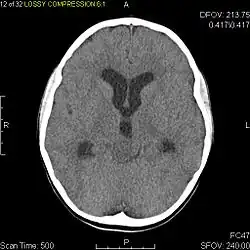

Axial non-contrast CT in a nine-year-old girl showing a slightly hypodense mass in the tectum of the brainstem, compressing the aqueduct of Sylvius and causing obstructive hydrocephalus

Usually – depending on the interview of the patient and after a clinical exam which includes a neurological exam and an ophthalmological exam – a CT scan and/or an MRI scan will be performed to confirm the presence of a tumor. They are usually easily distinguishable from normal brain structures using these imaging techniques. A special dye may be injected into a vein before these scans to provide contrast and make tumors easier to identify. Pilocytic astrocytomas are typically clearly visible on such scans, but it is often difficult to say based on imaging alone what type of tumor is present.